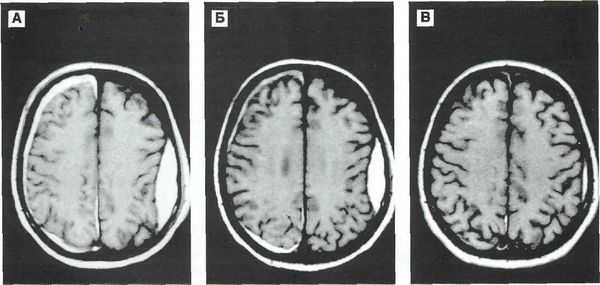

Решающими методами в диагностике субдуральной гематомы являются КТ и МРТ головного мозга. В диагностике острых гематом предпочтение отдается КТ головного мозга, которая в таких случаях выявляет однородную зону повышенной плотности, имеющую серповидную форму. С течением времени происходит разуплотнение гематомы и распад кровяных пигментов, в связи с чем через 1-6 нед. она перестает отличается по плотности от окружающих тканей. В подобной ситуации диагноз основывается на смещении латеральный отделов мозга в медиальном направлении и признаках сдавления бокового желудочка.

При проведении МРТ может наблюдаться пониженная контрастность зоны острой гематомы; хронические субдуральные гематомы, как правило, отличаются гиперинтенсивностью в Т2 режиме. В затруднительных случаях помогает МРТ с контрастированием. Интенсивное накопление контраста капсулой гематомы позволяет дифференцировать ее от арахноидальной кисты или субдуральной гигромы.